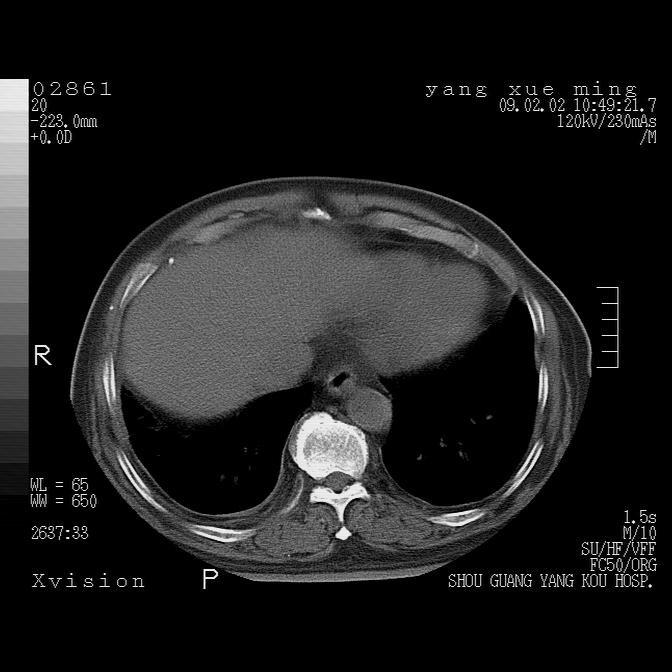

以下是引用lkc8963在2009-2-3 20:11:00的发言:[br]1)右上肺陈旧病灶。2)右下肺团块及团片影,影像表现符合感染。3)左心增大,左冠脉钙化,符合冠心病。4)双侧肺门扩大,以左侧为著,肺动脉干略粗,左上肺局限性气肿,为谨慎起见,需除肿瘤,建议增强。

以下是引用zbp537在2009-2-3 19:08:00的发言:[br]我诊断为肺泡性肺水肿。[br]诊断依据:[br]1、心影普遍增大,肺血管增粗,并见絮状高密度影,肺门改变显著。[br]2、临床上表现胸闷咳嗽,无发烧,不是一个典型的肺部感染的病史。

以下是引用王仕学在2009-2-3 20:28:00的发言:[br]考虑右下肺感染,建议治疗后复查。